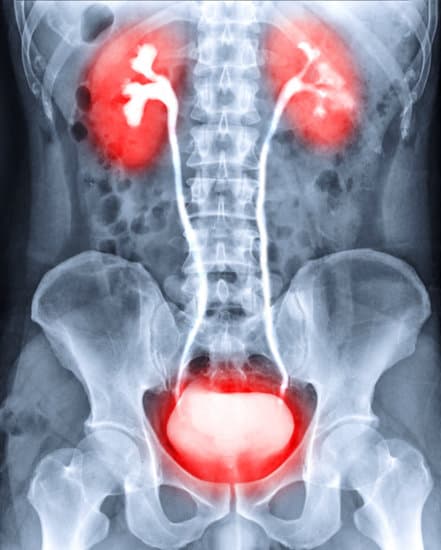

배뇨성 방광요도조영술(Voiding Cystourethrography) 개요

배뇨성 방광요도조영술(VCUG)은 소변이 방광에서 요도를 통해 배출되는 과정을 이미지로 촬영하는 의료 진단 방법입니다.

이 검사는 방광과 요도의 구조 및 기능을 평가하여 요로 감염, 요관 역류, 요도 폐쇄와 같은 여러 비뇨기 질환을 진단하는 데 사용됩니다.

방광 내에 특수 조영제를 주입한 후 X-레이를 통해 방광과 요도의 상태를 확인합니다.